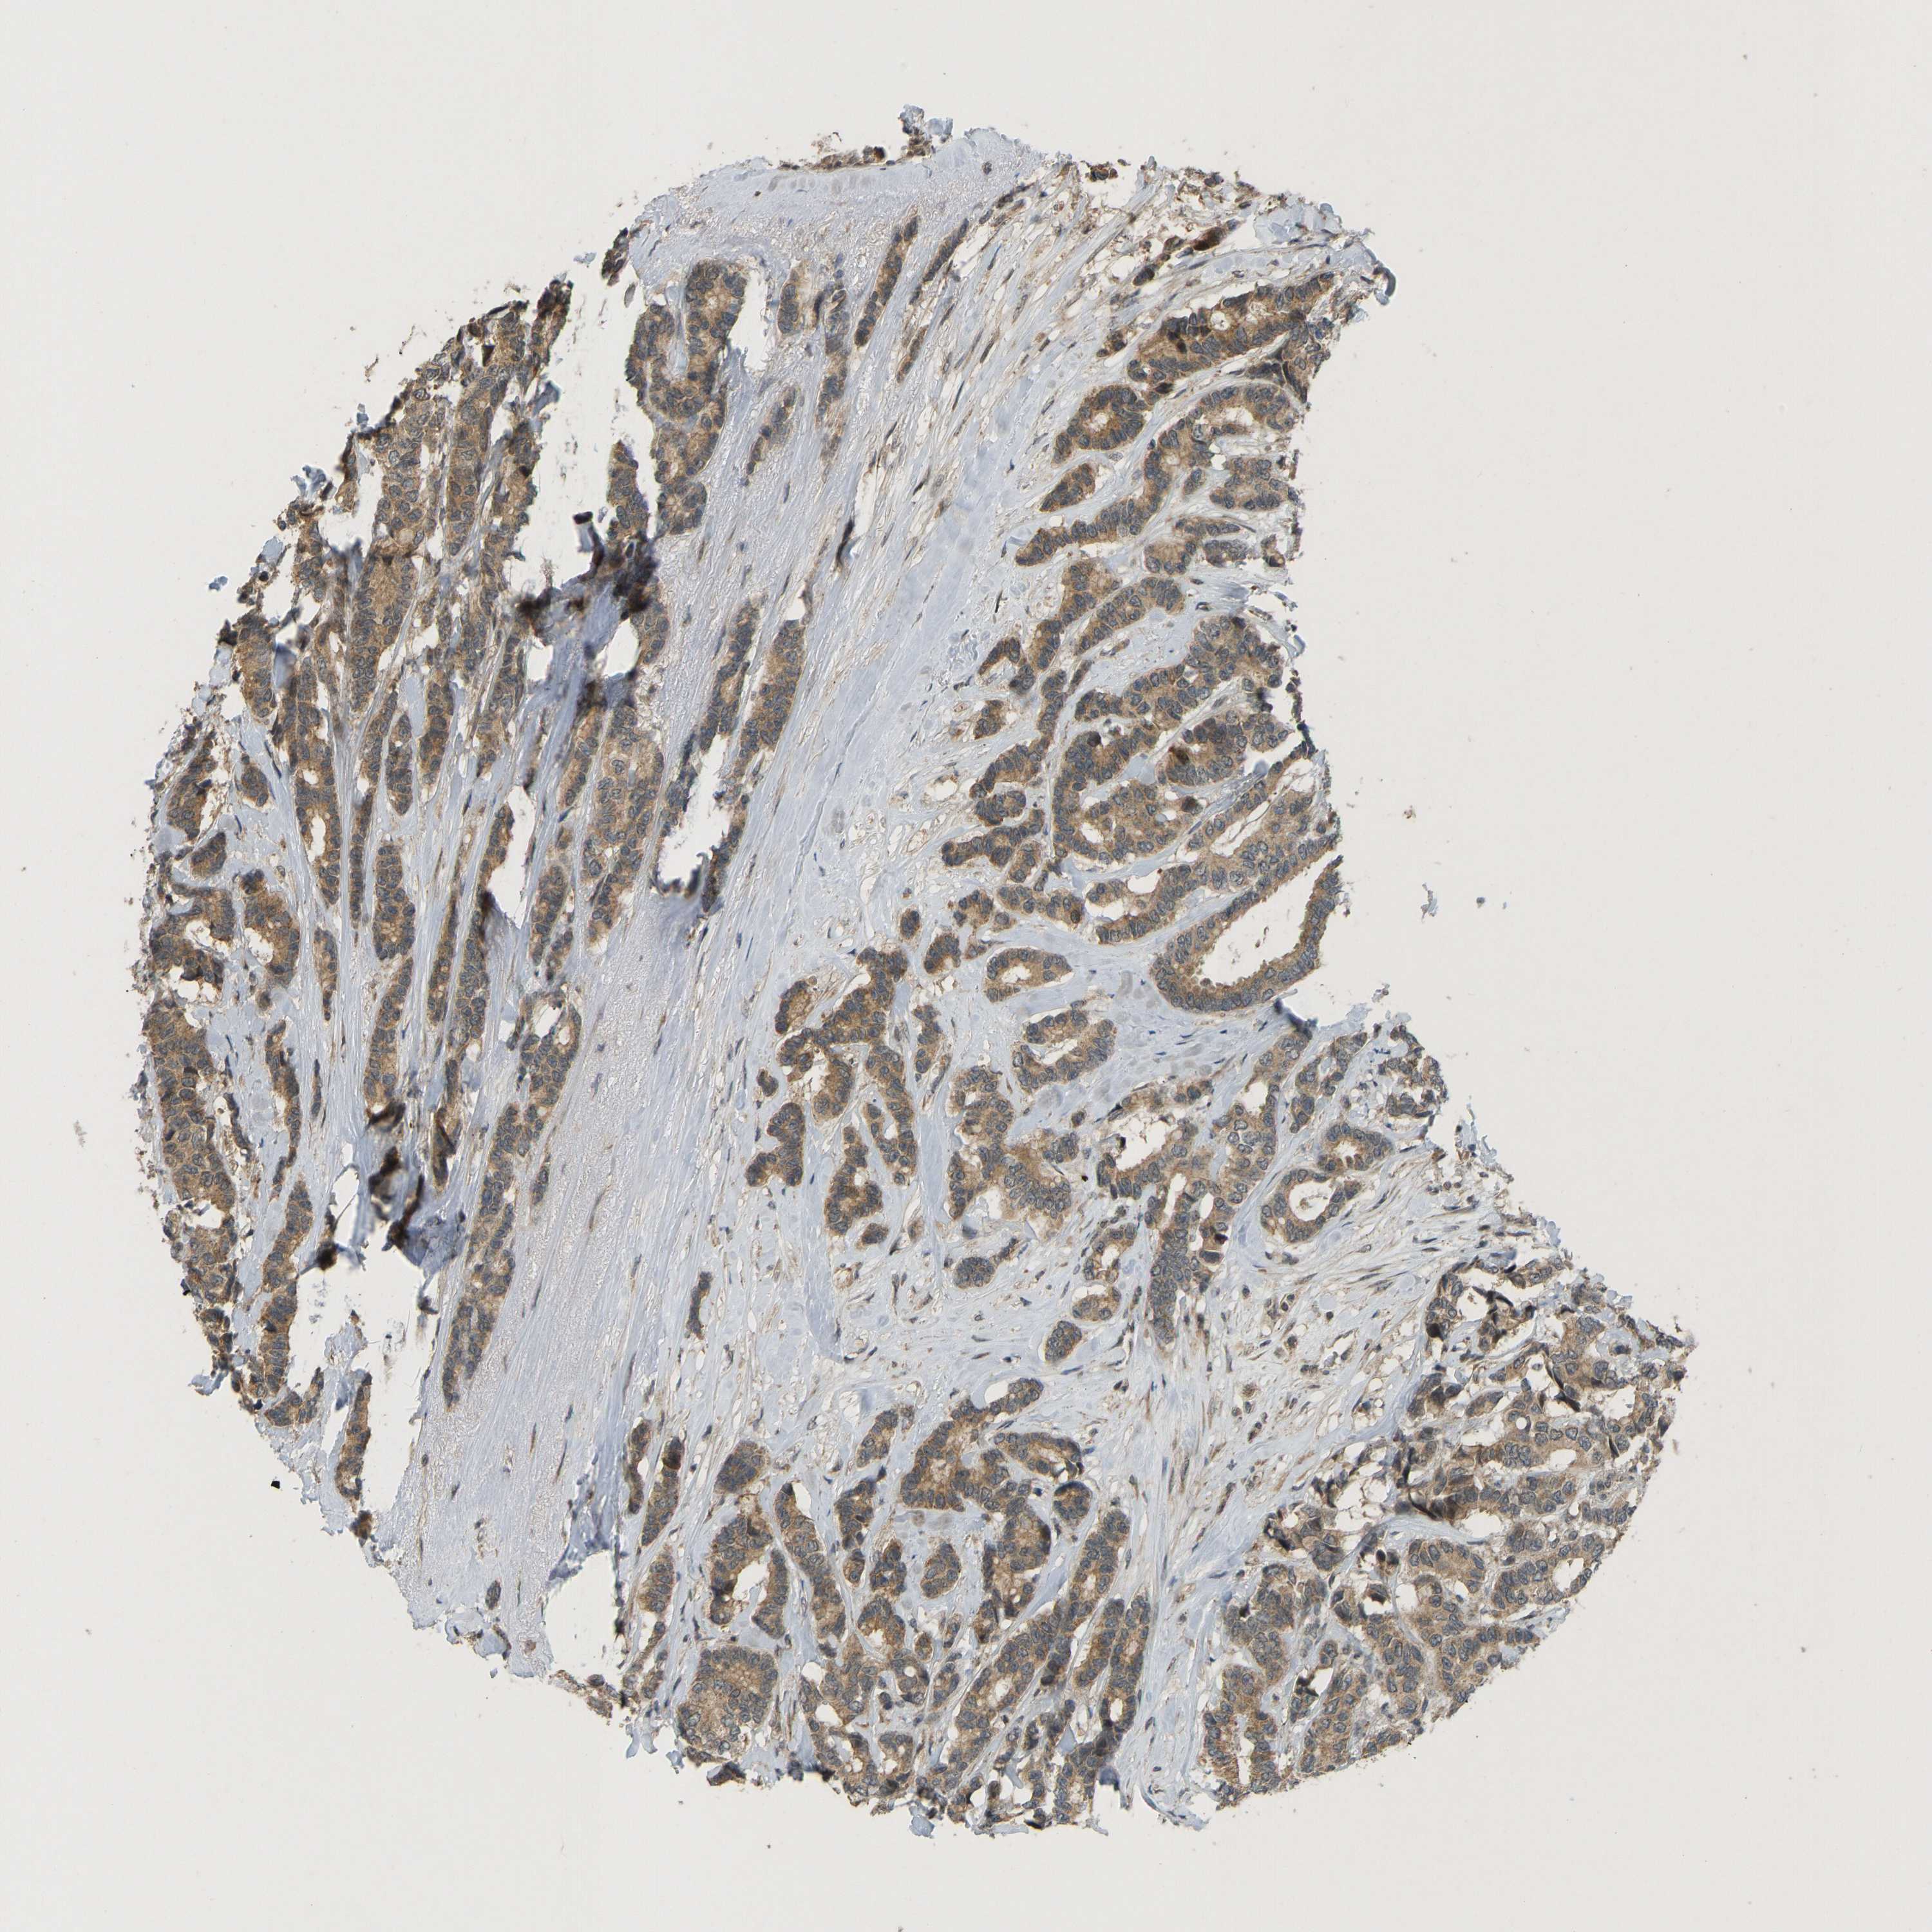

BRCA TCGA BRCA VALIDATION PROTEIN EXPRESSION

ANTIBODIES

AND

VALIDATION